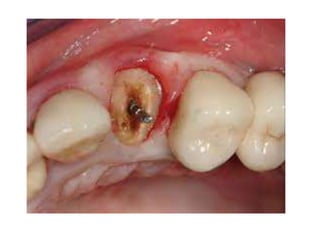

Post crown: it is an artificial

restoration of the coronal

portion of the natural tooth

maintained in position mainly

by post inserted in the

prepared root canal.

Post crown: itis an artificial restoration of the coronal portion of the natural tooth maintained in position mainly by post inserted in the prepared root canal.